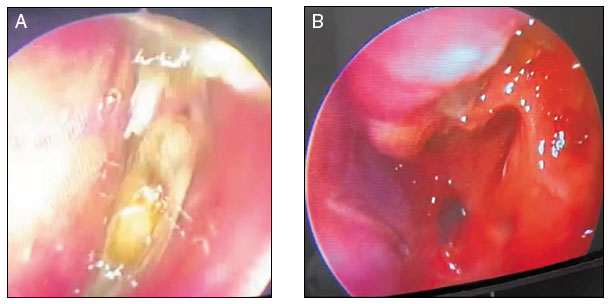

Figura 1

Endoscopia nasal pré-dupilumabe (A) e após 8 semanas de tratamento (B)

No caso relatado, a paciente apresentava todos os critérios clínico-laboratoriais estabelecidos para o diagnóstico de RSCcPN com inflamação tipo 2 (Tabela 1, Figura 1)16. Evoluiu com piora clínica progressiva, caracterizada pela recorrência dos pólipos, refratários aos tratamentos clínico e cirúrgico, coexistência de asma não controlada, resultando em perda significativa da sua qualidade de vida. Considerando a gravidade do quadro clínico, especialmente pela recorrência dos pólipos e uso frequente de corticosteroides sistêmicos, optou-se por iniciar o dupilumabe, 300 mg SC a cada duas semanas, na tentativa de controlar o processo inflamatório nasal. Após oito semanas, evoluiu com melhora clínica significativa, corroborada pelos escores SNOT-22, EVA e NPS, mantendo a asma controlada pelo ACT (Tabela 2). A paciente não apresentou nenhum evento adverso durante o período.